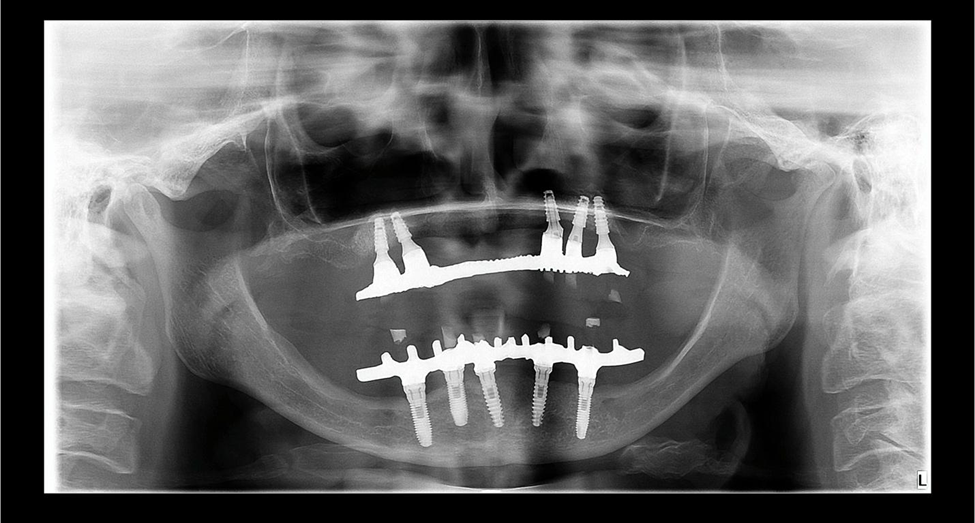

Realizamos a cirurgia de instalação dos implantes (Maestro CM, Implacil De Bortoli) sob sedação endovenosa e monitoramento por médica anestesista em nosso consultório cirúrgico. A radiografia panorâmica pós-operatória mostra a distribuição dos implantes (Foto 5). A prótese total da paciente foi aliviada internamente e reembasada com material macio (COE-SOFT) para que pudesse ser utilizada durante o tempo de Osseointegração dos implantes (seis meses).

A cirurgia de reabertura dos implantes foi realizada com instalação simultânea dos componentes protéticos e moldagem para dar início ao processo de confecção da prótese protocolo. A variedade de componentes protéticos disponíveis na Implacil De Bortoli foi primordial nesse caso, onde, devido à proximidade dos implantes do lado esquerdo e visando facilitar a higienização da área e reduzir as chances de um processo de peri-implantite, utilizamos um componente mini cônico angulado e um componente micro cônico reto nos implantes das regiões de 23 e 24, respectivamente. O uso destes componentes possibilitou um bom eixo de saída dos parafusos protéticos e a manutenção de espaço entre eles. A radiografia panorâmica final e as fotos clínicas apresentam a finalização do caso com a reabilitação protética (Fotos 6, 7 e 8).